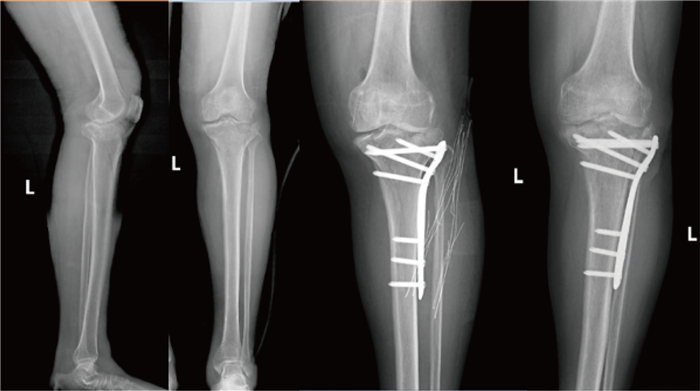

1 临床资料 1.1 病例特点患者,男性,60岁,2022年6月3日骑电动车时不慎与小轿车相撞,摔倒在地,感左膝部疼痛,伴活动受限,不能站立及行走。至我院急诊科就诊,行电子计算机断层扫描(Computed Tomography,CT),见:左胫骨近端粉碎性骨折,累及膝关节面,断端对位对线尚可;左侧腓骨小头骨折,断端对位对线良好;左膝关节少量积液;左膝关节周围软组织肿胀(X片见图 1)。一般血液检查结果如图 2所示。

| 图 1 下肢正侧位X片 Fig. 1 Anteroposterior and lateral x-rays of the lower limbs |